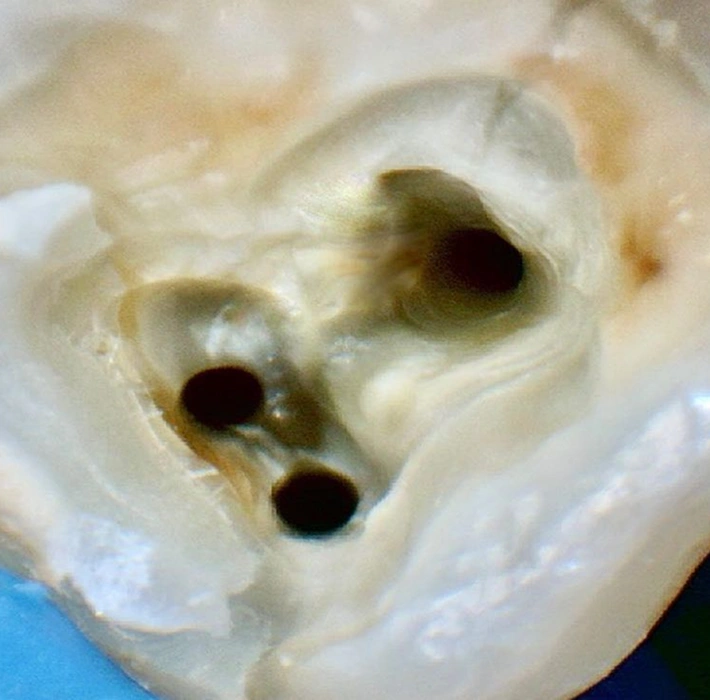

Tratamento Endodôntico (Canal)